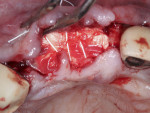

A 60-year-old male patient presented with a hopeless maxillary right central incisor, edentulous maxillary left central incisor, and hopeless maxillary left lateral incisor. Because minimal tooth structure was available for extraction of the maxillary left central incisor, a sulcular incision was placed extending from the maxillary right canine to the maxillary left canine, and a full-thickness flap was elevated. Extraction was completed followed by degranulation of the sockets. A 5 mm deep buccal dehiscence was noted at the site of tooth No. 8. A 3 mm buccal plate dehiscence as well as a 3 mm diameter buccal plate fenestration were observed at the apex of tooth No. 10. Adequate bone to support immediate implant placement was noted, and implantation (BioHorizons Tapered Internal) was completed at sites Nos. 8 and 9, followed by the placement of 0 mm height cover screws (Figure 7 and Figure 8).

Adequate bleeding bone was observed; therefore, intramarrow decortications were deemed unnecessary in this case. A freeze-dried bone allograft composed of a 50/50 mix of cortico-cancellous graft material was then adapted to the sockets and buccal plate of sites Nos. 8 through 10. A sugar-crosslinked collagen membrane (25 mm x 30 mm) was then hydrated and adapted over the buccal occlusal palatal line angle. Due to the size of the edentulous span and addition of bone graft materials, the membrane was unable to fully cover the bone graft, and 2 mm to 3 mm of graft material was exposed on the mesial and distal aspects. A 20 mm x 30 mm dHACM was placed over the surgical site and extended past the defect margins mesially and distally 3 mm to 4 mm in both directions. Two periosteal biting stabilizing sutures were then placed with a resorbable suture to stabilize the collagen and amnion/chorion membranes over the graft material (Figure 9). Two horizontal mattress sutures with 3-0 PTFE were placed 5 mm to 7 mm from the soft-tissue margins to initiate tension-free primary closure. Additional single interrupted sutures using the same 3-0 PTFE were also utilized to complete primary closure (Figure 10).